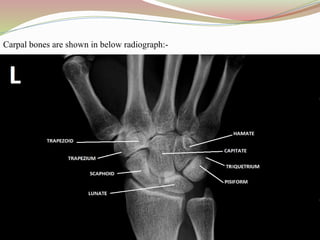

Carpal bones are shown in below radiograph:-

Carpal bones areshown in below radiograph:-

CARPAL INJURIES

DEFINITION: This is a fracture of one or more of the eight carpal bones of the wrist

located between the radius and the ulna bones of the forearm and the metacarpal bones

of the hand.